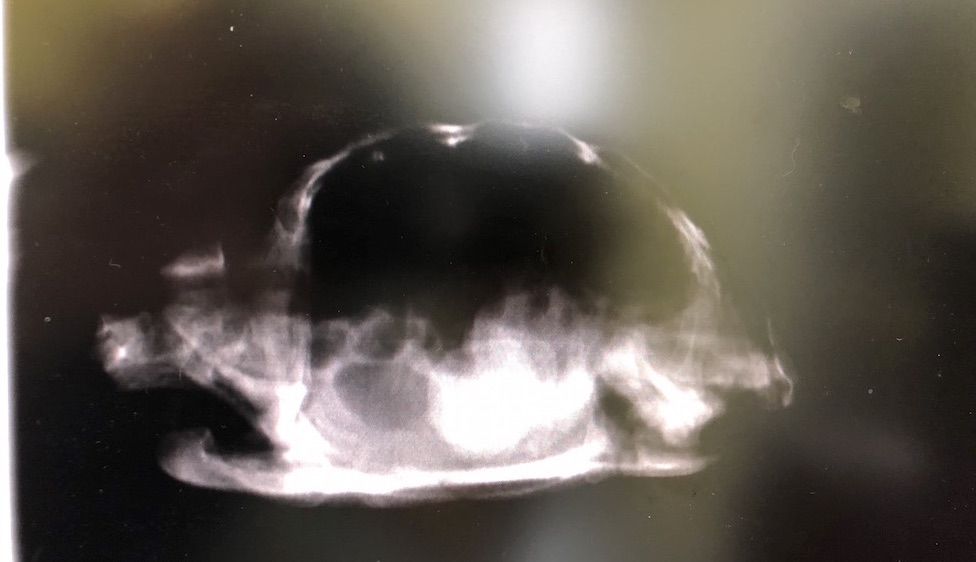

状況を説明した後、詳細を把握するために再度レントゲンの撮影を行います。

横からの画像に驚きました。

ここまで大きな石を抱えていたとは・・・

位置やサイズを考慮すると骨盤付近まで下りてくることは期待できず、タイガーを救う手段は早急な開腹手術しかなさそうです。